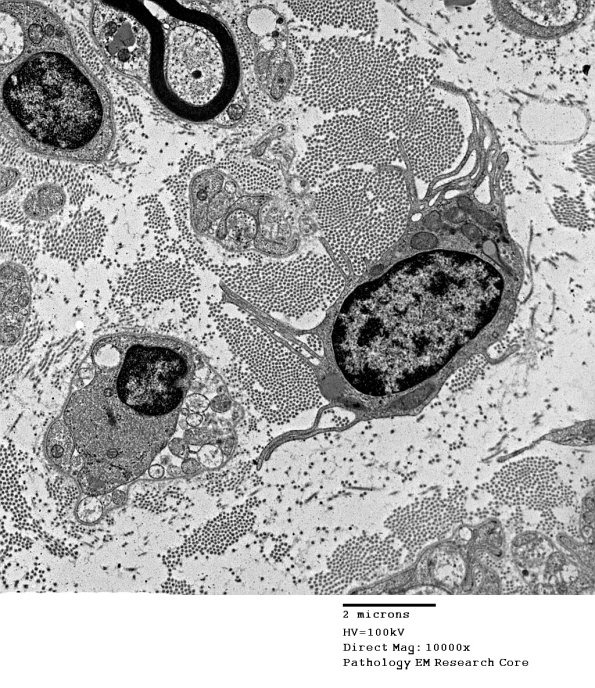

A macrophage exhibiting prominent processes but without significant phagocytosed material is shown moving through the endoneurium in a case in which there is significant axonal degeneration.